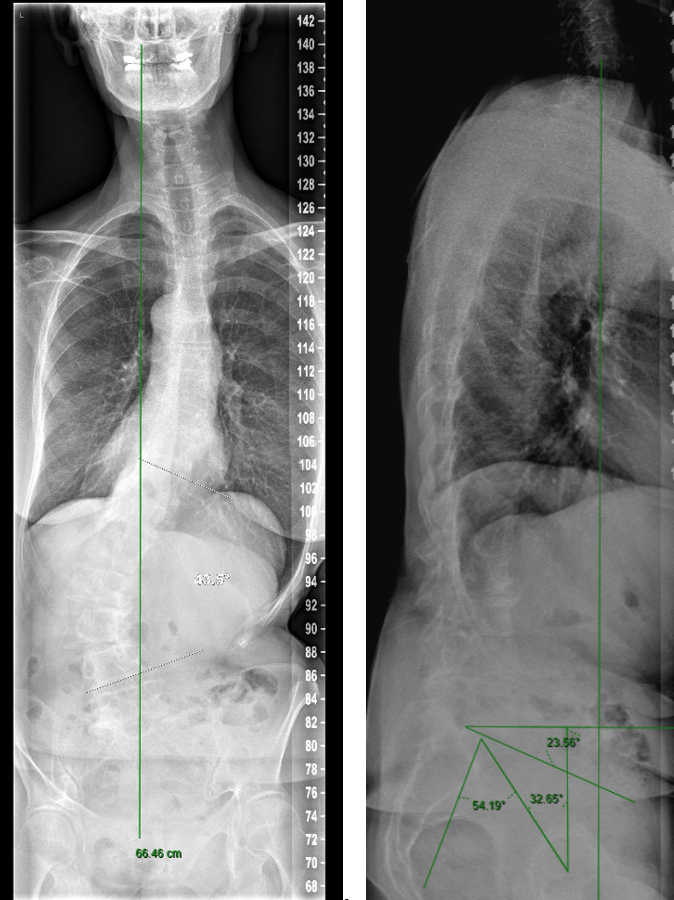

A 70-year-old woman with an adult spinal deformity (ASD) was referred to our hospital for a second opinion. Her medical history included rheumatoid arthritis for which she was given long-term methotrexate therapy and cures of corticosteroids. She presented with a severe degenerative deformity and right L3 radiculopathy. The patient was completely off balance with a right coronal shift and a positive sagittal balance with a SVA of 10 cm+ (Fig 4). Figure 5 reveals full spine images and pelvic parameters. She led a sedentary lifestyle because of the disturbance of balance and back and right leg pain. The patient opted for surgery after a shared decision process and informed consent.